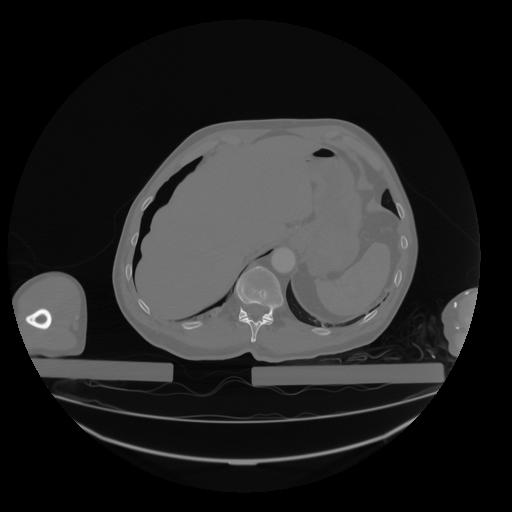

28 CUERPO,CE,Vol,2.0,CUERPO,,